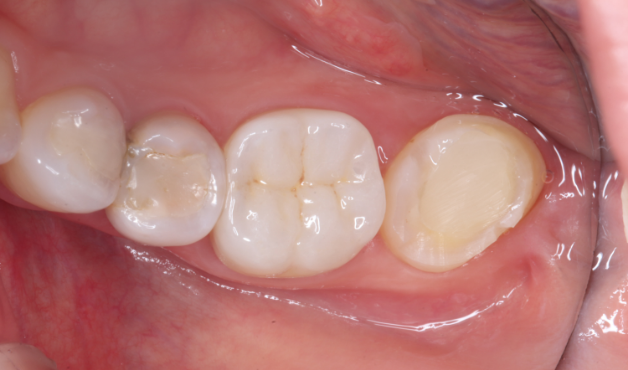

Before

After

主訴

歯を抜いた後インプラントが必要と言われた。

治療内容

自家歯牙移植 / イニシャルトリートメント(大臼歯)レジンコア / ジルコニアクラウン / 概形成・TEK作成 / 精密形成・TEKリマージン

治療期間

3ヶ月

治療費用

462,000

治療の

リスク

術後しばらくしてから骨性癒着、外部吸収を起こす可能性があります。